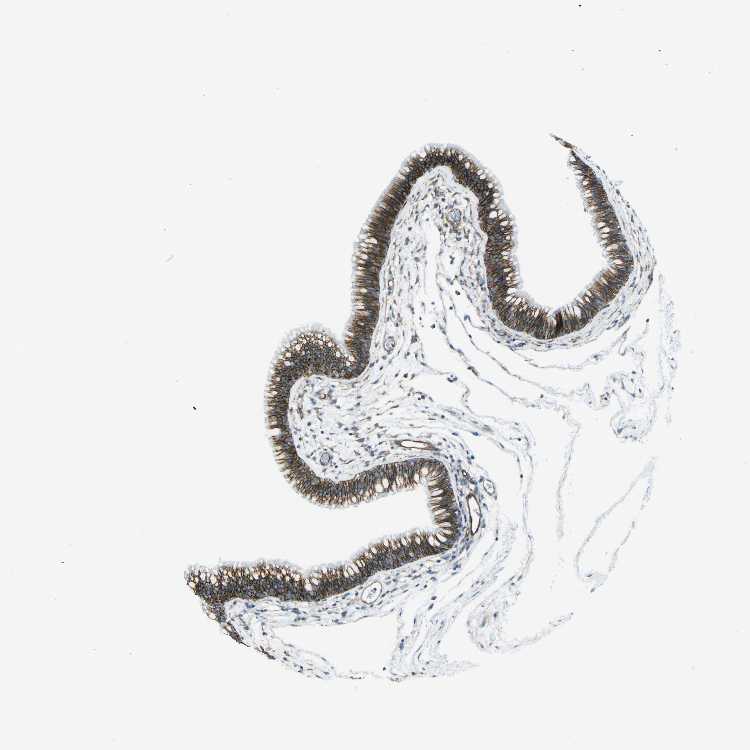

TISSUE PRIMARY DATA NASOPHARYNX Show tissue menu

NASOPHARYNX - Antibody stainingi

Antibody staining in the annotated cell types in the current human tissue is reported as not detected, low, medium, or high, based on conventional immunohistochemistry profiling in selected tissues. This score is based on the combination of the staining intensity and fraction of stained cells.

Each image is clickable and will lead to virtual microscopy that enables deeper exploration of all samples and also displays staining intensity scores, fraction scores and subcellular localization as well as patient and tissue information for each sample.

Antibody HPA018894Antibody CAB016348

Respiratory epithelial cells MediumHigh